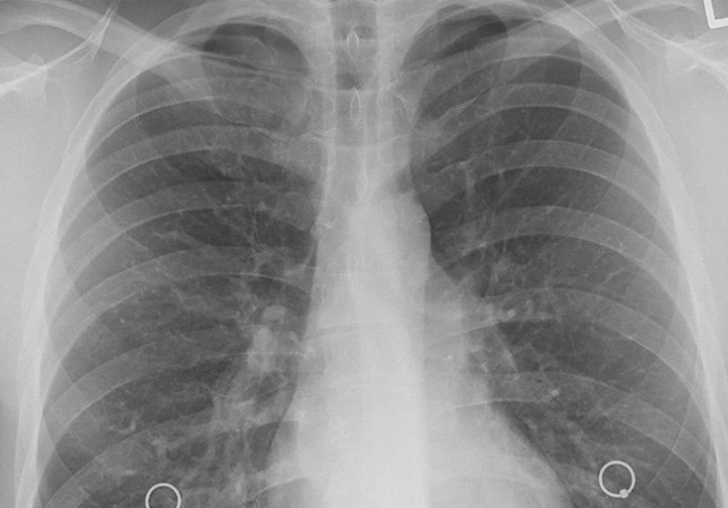

Kanser ölümlerinde ilk sırayı akciğer kanserinin aldığına işaret eden İtil, "Türkiye'de her yıl yaklaşık 35 bin insan akciğer kanseri tanısı alıyor. Ülkemiz, erkeklerde 100 bin kişide 41,7 oranı ile dünyada akciğer kanserinin en çok saptandığı ülkelerden biridir ve akciğer kanserinin en önemli nedeni halen tütün ürünleridir." ifadesini kullandı.

Prof. Dr. İtil, sigara, puro, piponun yanı sıra özellikle gençlerin tercih ettiği elektronik sigaraların masum olmadığının altını çizerek, ayrıca asbest, radon gazı ve hava kirliliğinin akciğer kanserinin önemli nedenleri arasında yer aldığını belirtti.

"Herkese, akciğer kanserinden korunmanın halen en başarılı yolunun tütün ürünü kullanmamak, sigara dumanına maruz kalmamak ve en kısa zamanda sigaradan kurtulmak olduğunu hatırlatmak istiyoruz" uyarısını yapan İtil, şikayetleri olanların mutlaka maske, mesafe önlemlerini alarak hastanelere başvurmasının önem taşıdığını vurguladı.

Dünyada birçok ülkenin akciğer kanseri tarama programlarını başlattığını ya da pilot çalışmalar yaptığını aktaran Öncel, "Ülkemizde tütün ürünlerinin kullanım düzeyinin yüksek olması ve akciğer kanseri vakalarında görülen yüksek oranlar nedeni ile bu konuda farkındalığın artması ve akciğer kanseri tarama programları için pilot çalışmaların başlatılması gerektiğini düşünüyoruz." değerlendirmesinde bulundu.